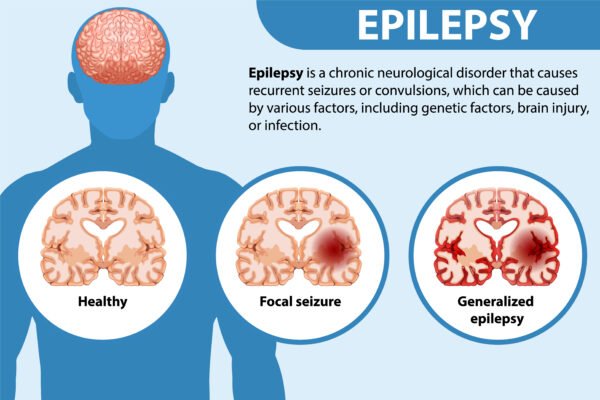

- Epilepsy